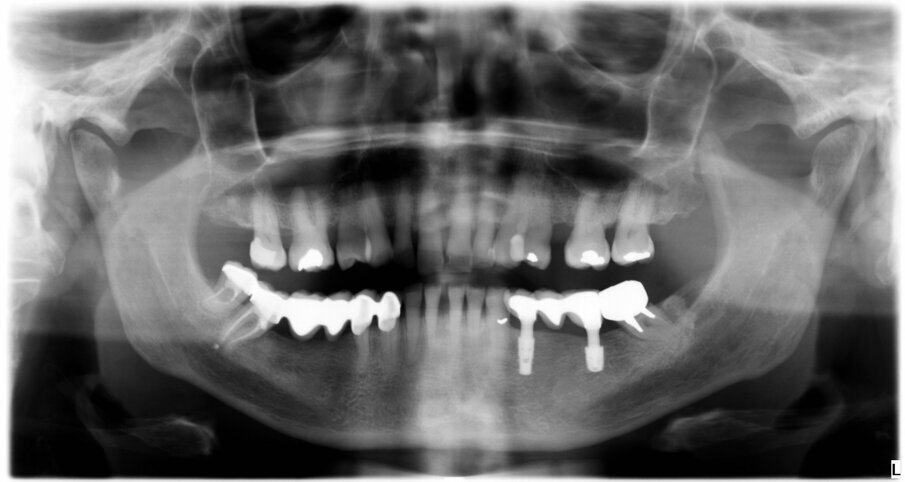

The female patient was 59 years old and had no noteworthy medical history, except for degenerative osteoarthritis of the left hip joint and compensated hypertension. She complained of chewing pain in the third quadrant. On physical examination, she presented with an old-fashioned bridge prosthesis with partial mobility, loaded on natural teeth. After radiographic evaluation with a dental panoramic tomogram of the dental arches, tooth #34 appeared devitalised, and tooth #37 appeared devitalised and a fused post-abutment was mesialised and considerably inclined (Fig. 1).

It was evident that tooth #34 had to be extracted. Despite the overload of tooth #37, the patient refused its extraction because it was not painful. We therefore proceeded with the separation of the existing bridge, maintaining the coverage of tooth #37 and the exposure of the edentulous part. Subsequently, the extraction of tooth #34 was performed. A CBCT assessment of the mandibular dental arch was performed, and the insertion of a 3.6 mm diameter and 9.0 mm long GTB implant in position #34 and of a 4.3 mm diameter and only 6.0 mm long GTB implant was planned (Fig. 2). This last choice was necessary not to avoid contact with the inferior alveolar nerve but because of the presence of a very high mylohyoid line and the consequent inclination of the lingual bone wall of the mandible below that line. We favoured the prosthetic axis of the implant rather than a greater length of the implant, which is obtainable by tilting it in a lingual–buccal direction. The surgical planning was performed according to the surgical protocol for GTB implants, which provides for the flattening of the knife blade ridge, the positioning of implants in the prosthetic axis and sinking the implant to the sub-crestal level of 1.5 mm. During surgery, we obtained an insertion torque of 25 Ncm in position #34 and of 20 Ncm in position #36 (Figs. 3a & b).